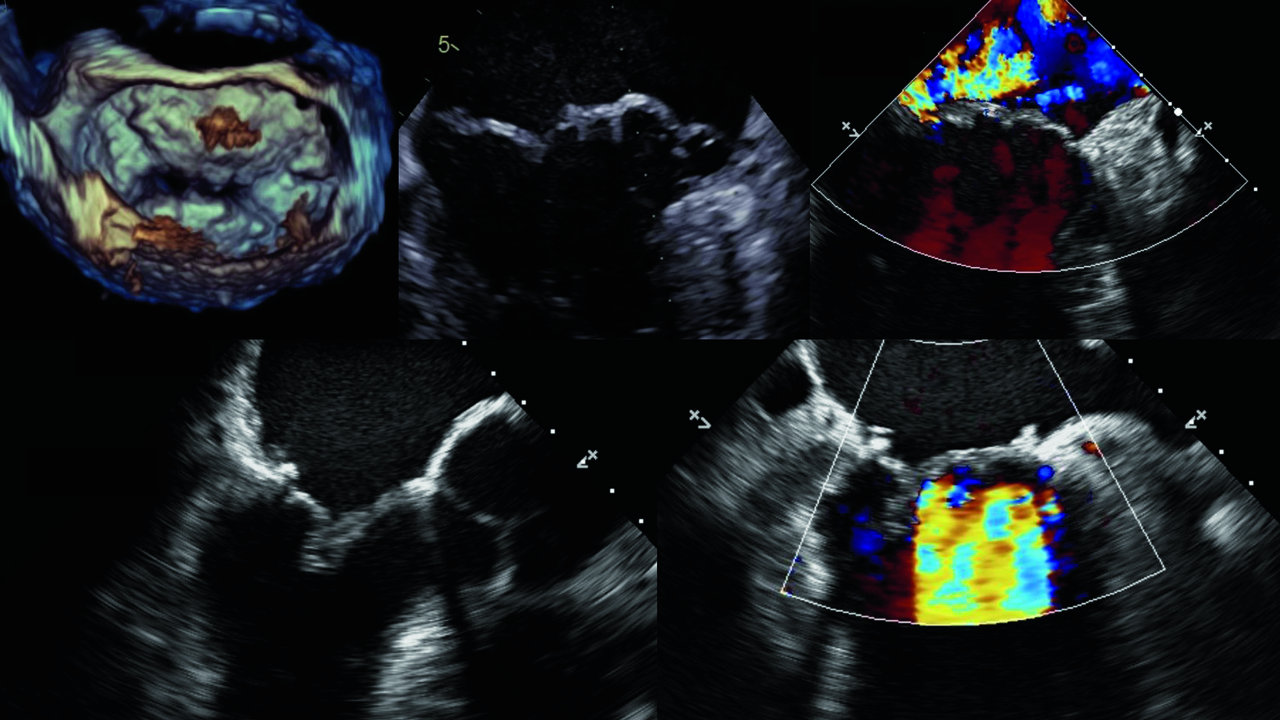

Die aktuelle Echokardiographie zeigte eine Progression des Klappenvitiums mit hochgradiger Insuffizienz und einem Prolaps beider Segel. Auch die Trikuspidalklappe war bereits geschädigt. Zudem fand sich ein kleiner Vorhofseptumdefekt. Die Kardio-CT ergab eine erhebliche Vergrößerung des Herzens, war aber ansonsten unauffällig. Aufgrund dieser Konstellation entschieden sich die Kollegen für eine Doppelklappenreparatur via Sternotomie.

Die OP erfolgte wegen einer hochgradigen Mitralklappeninsuffizienz im Sinne eines M. Barlow. Zu erkennen ist der Reflux in den linken Vorhof.